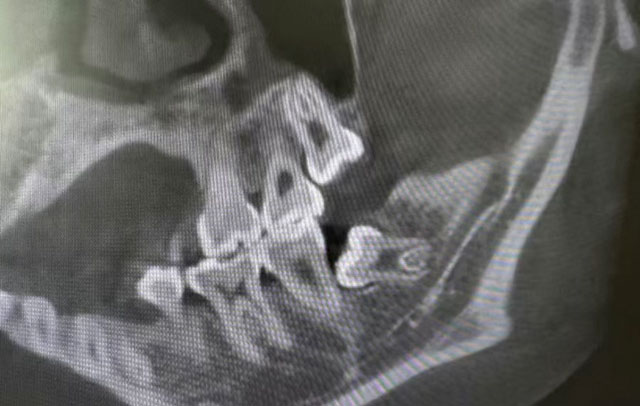

總結(jié)來說,一個人長不長智齒都是正常的,只長1顆或長全4顆也都有可能。那么問題來了,很多人其實是不知道自己有幾顆智齒的,因為一些智齒并不會完整萌出,有些甚至完全埋伏在牙槽骨里,需要拍片才能發(fā)現(xiàn)。

先說6號牙,它是最早長出來的恒磨牙,是人一生中使用時間最長的磨牙。小朋友或家長沒有做好清潔的話,非常容易齲壞,嚴(yán)重齲壞后到了成年階段就容易形成缺損和缺失。至于7號牙,可能并不是自身的問題,它的齲壞、缺損和缺失往往和8號牙有關(guān),是由“隔壁”長得不正的智齒一手造成。位置不正的智齒,不管是完全萌出、部分萌出還是以埋伏阻生的姿態(tài)“潛伏”在牙槽骨里,對7號牙來說都是隱患。